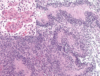

Figura 28. 1 Astrocitos reactivos. La tinción inmunohistoquímica para la proteína gliofibrilar ácida (morrón) pone de relieve las prolongaciones astrocíticas estrelladas que dan nombre a estas células.